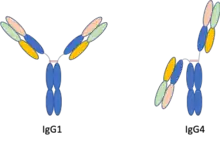

The clonality of plasma cells is most accurately determined by two different methods.[3] One method is flow cytometry and the other is kappa/lambda in-situ hybridization and/or immunohistochemical staining (IHC). To obtain the most precise results of clonality it is recommended that both methods be used.[12] Flow cytometry is generally carried out with plasma cell granulomas to obtain the ratio of kappa light chains to lambda light chains.[3] Immunohistochemical staining of plasma cell granulomas is an important diagnostic method to show PCG lesions are also an entity within the IgG4-related diseases.[3] IHC staining is especially helpful because it allows for the assessment of the quantitative number of IgG4 positive plasma cells.[3] Immunohistochemical staining will also provide the overall ratio of IgG4 secreting plasma cells to the total number of IgG secreting plasma cells within a given mass.[3] Plasma cell granulomas have been characterized showing a ratio of IgG4:IgG of greater than 40 percent.[3] A ratio above 40 percent indicates abnormal elevated levels of IgG4 positive plasma cells.[3] Even though IgG levels can be measured in serum, histopathological analysis has been concluded to be the most accurate characterization method of PCG lesions.[3] Using serum IgG4 levels can be a misleading diagnostic, considering that up to 40 percent of patients diagnosed with plasma cell granuloma have IgG4 serum levels within normal reference ranges.[3]